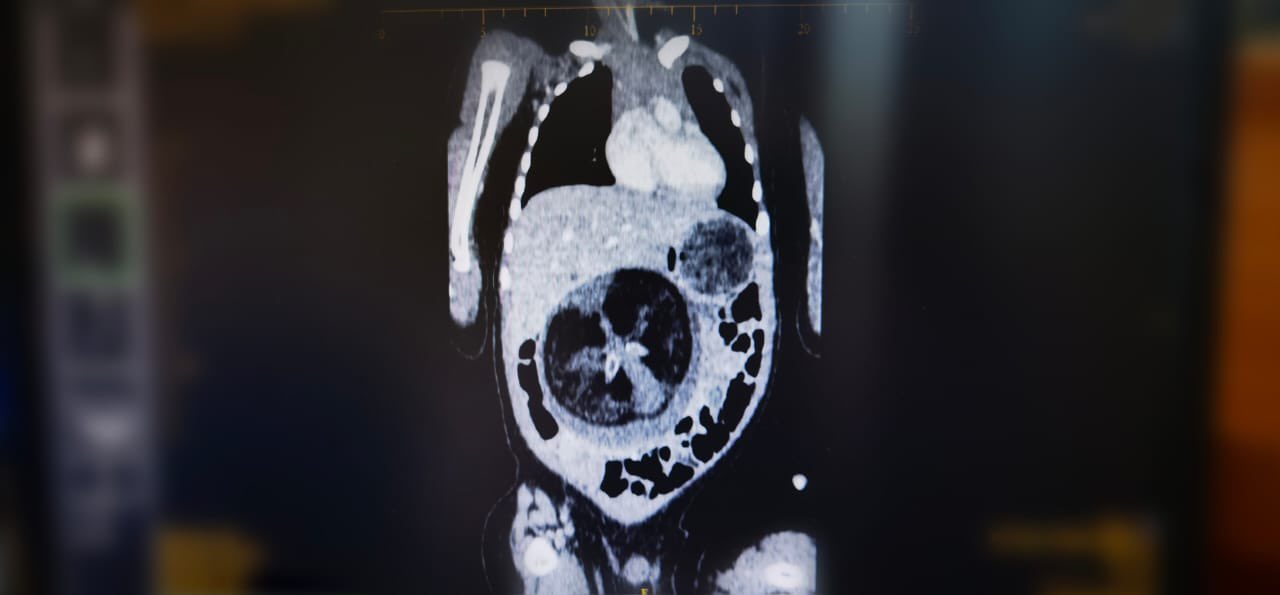

أجرى قسم جراحة الأطفال بالمستشفى السلطاني عملية جراحية نادرة تتمثل في استئصال جنين من داخل جنين، وهي حالة تعد نادرة الحدوث عالميا، لكونها تتم في ظروف استثنائية.

وأُجريت العملية لطفل يبلغ من العمر ثمانية أشهر،وبعد ثلاثة أيام من إجراء العملية تم التحقق من الفحوصات والمؤشرات التي أثبتت نجاح هذه العملية النوعية وسمح للطفل بمغادرة المستشفى.

يُذكر أن هذه الظاهرة الطبية تعرف ب” Fetus in feto” وتحدث بنسبة 1 من كل 500 ألف حالة ولادة حية على مستوى العالم.